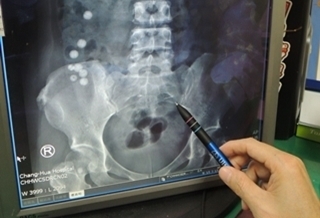

(優活健康網記者徐平/綜合報導)一名2歲大的男童在洗澡時,突然喊手痛,爸爸仔細看了他的左手才發現手掌上有一小塊瘀青,只要朝瘀青的部分輕微下壓兒子就會喊痛。家長覺得不對勁,將男童帶往醫院才發現小瘀青竟包圍著0.5公分大的玻璃碎片,原來是男童先前打破玻璃罐,玻璃碎片藏在左手掌上長達2個月才導致瘀青出現。2、3歲好奇心旺盛 容易造成許多危險2、3歲時正是好奇心旺盛的時候,不論見到甚麼東西都想嘗試,也就容易增加許多危險。患者媽媽表示,兒子最近很喜歡自己開冰箱拿東西,受傷的那天早上,自己到冰箱拿了一罐剝皮辣椒玻璃罐,走到一半時突然打破,當時以為只有一塊小玻璃卡在大拇指處,沒想到還有另一片藏在手掌裡。豐原醫院傷口照護科主任陳明澤表示,雖然患者外觀上沒有明顯傷口、或是凸起來的東西,但是仔細摸,仍感到有硬硬的東西,從X光中得第三指處,也能夠看到一個類似玻璃的東西。身體防禦機制會把異物變肉芽腫塊陳明澤主任表示,因為異物在手中本身就不容易找到,主要是不知道異物藏在肉的哪一層裡,常有些患者因異物卡的太深,必須整個肉都要挖除,甚至要找1、2小時以上,幸好此次定位精準,才能在30分鐘內就找到了這個0.5公分大的厚玻璃碎片。 陳明澤提醒,如果異物沒有及時取出可能會造成感染發炎,即使傷口沒有發炎,身體的防禦機制把異物變成肉芽腫塊,導致患者摸到這個部位,就會覺得硬硬不舒服,因此建議一有傷口應盡快就醫,才能及早治療。